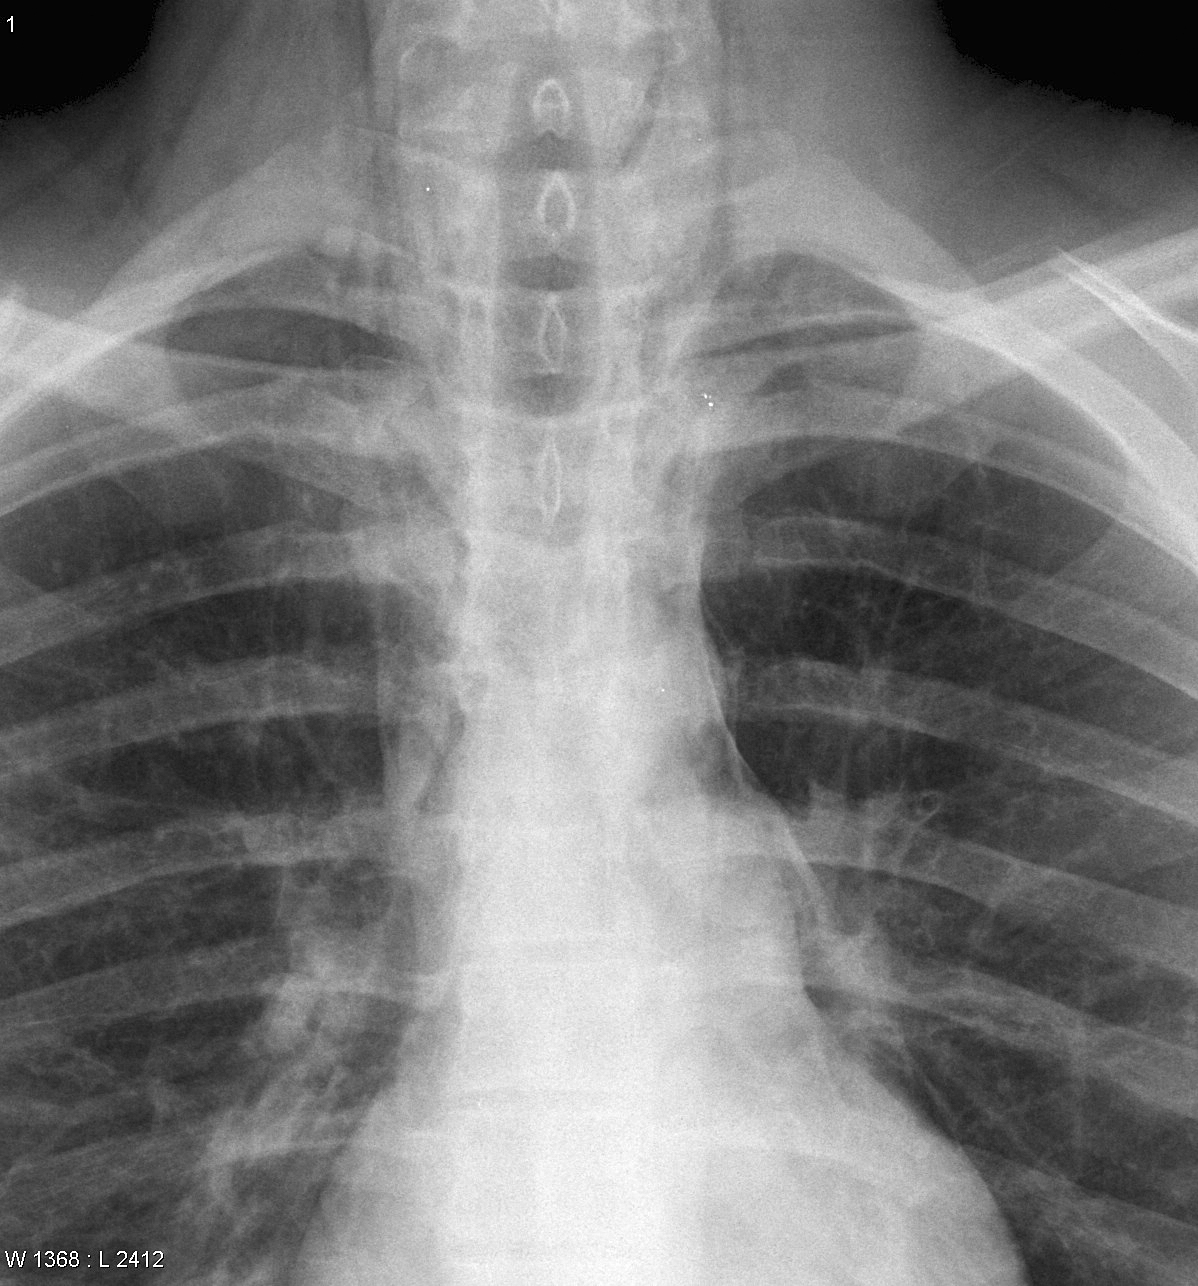

Mediastinum

Miscellaneous

Pneumomediastinum cu